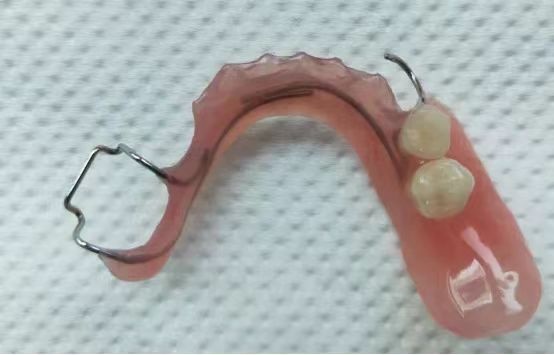

可摘式间隙保持器

主要适用于单颗或多颗乳牙早失的治疗,在保持间隙的同时,还能恢复部分咀嚼功能。